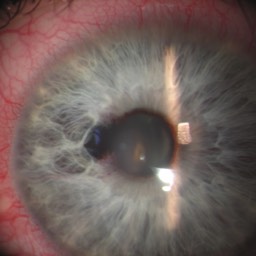

=> une déformation progressive d'une pupille qui n'est plus ronde,

=> l'apparition de tâches colorées sur l'oeil,

Quelques pathologies ophtalmologiques du segment antérieur